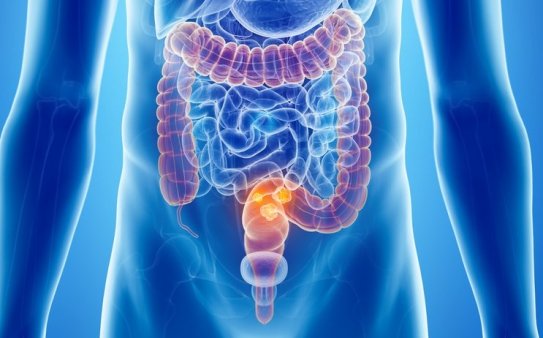

Рак прямой кишки

Рак прямой кишки – самое распространенное опухолевое заболевание пищеварительного тракта. Новообразование, состоящее из злокачественных клеток измененного эпителия, склонно к бесконтрольному росту и прорастанию в соседние органы, что приводит к утрате жизненно важных функций, мучительным болям, а при отсутствии медицинской помощи – к летальному исходу. Опухоль наиболее часто развивается у зрелых и пожилых людей в возрасте более 45 лет, соотношение между заболевшими мужчинами и женщинами составляет примерно 3:2. Среди онкозаболеваний эта разновидность рака занимает третье место по заболеваемости и смертности.